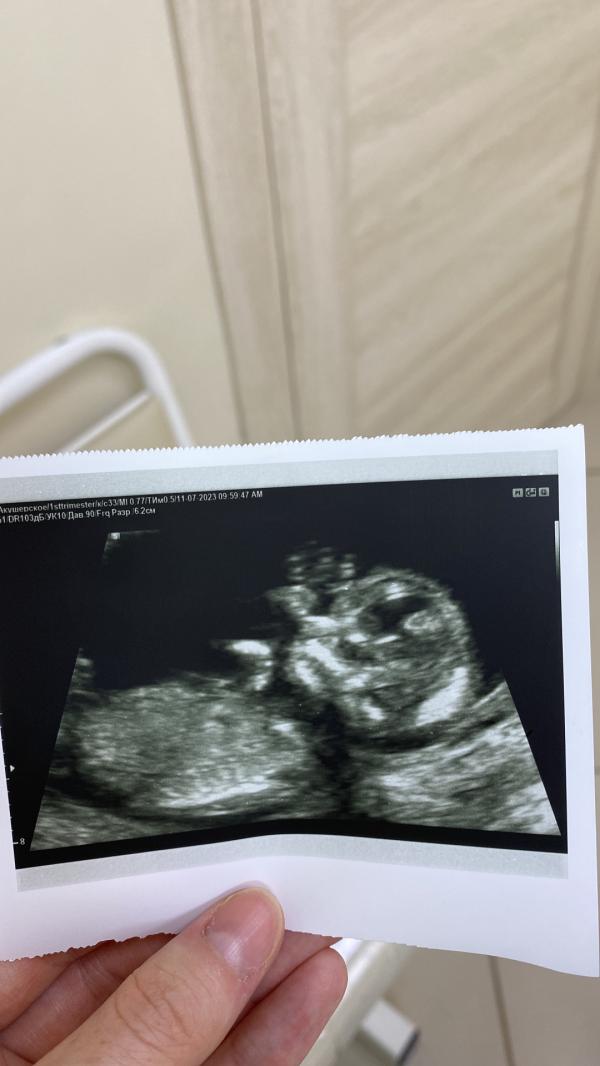

Прошла сегодня первый скрининг. Срок по узи поставили 13.2 дня, опережает на пару дней.

Мне так понравилось в этом жк, даже фотку мне распечатали) в первый раз тут проходила скрининг, весь персонал такой приятный.

Ну какая же классная фотка получилась 😍💕